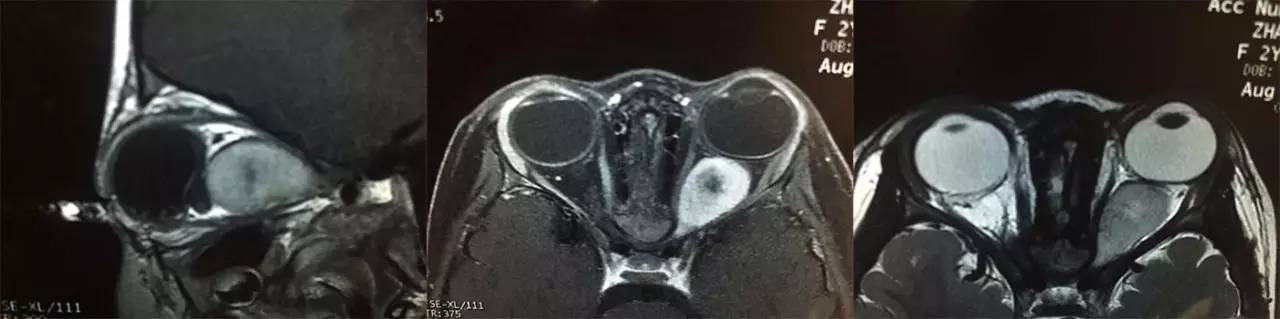

患儿男性,3岁,主因左眼突出3个月,伴左眼眼球向内偏斜1个月就诊。3个月前患儿家长发现患儿左眼轻度突出,突出不明显故未予诊治;近1月来,患儿左眼突出加重,并出现眼球向内偏斜,故就诊于北京同仁医院眼肿瘤专科门诊。患儿自发病以来,无眼红、眼痛、流泪增多等症状。全身查体:神志清、精神可,心、肺、腹未见异常,皮肤未见异常。眼科查体:视力右眼0.5左眼0.1,眼压 右眼16mmHg,左眼22mmHg。左眼眼球突出,内斜约10度,运动受限,角膜透明,瞳孔直径约5mm,直接对光反射消失、间接对光反射存在,KP(-),眶压可;右眼未见异常。眼底检查:左眼视盘水肿,黄斑中心凹反光不清;右眼底未见异常。眼眶MRI扫描显示,左眼眶肌锥内一梭形肿块,来源视神经,边界清,大小约30X15mm,视神经管扩大,眼球受压变形;T1WI相示病变为稍高信号,不均匀,内可见低信号区,T2WI相示病变为高信号,肿物边缘可见低信号,增强扫描后可见肿物不均匀强化,中心低信号区未强化;右眼未见异常。考虑左视神经胶质瘤可能性大(图1)。患儿在全麻下行左眶内肿物切除术,术中见肿物来源视神经,视神经明显增粗,病理组织学证实为左视神经胶质瘤。术后请儿科和放疗科进一步诊治。随访至今4月余,未见复发及转移迹象。

图1. 患儿术前MRI影像